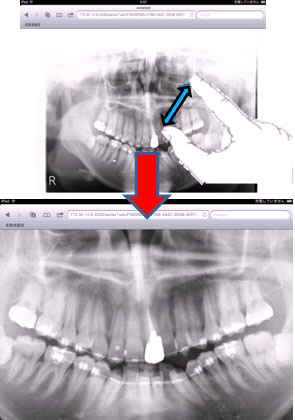

新規で撮影されたモダリティ(CR,CT,RG)のDICOM画像は,PACSサーバに保存され,OsiriXサーバ(iMac)に自動転送される(図8)。iPad2のWebブラウザから,患者IDを入力しiMacに保存された画像を参照する(図9,10)。

図9 iPad2での画像参照例 |